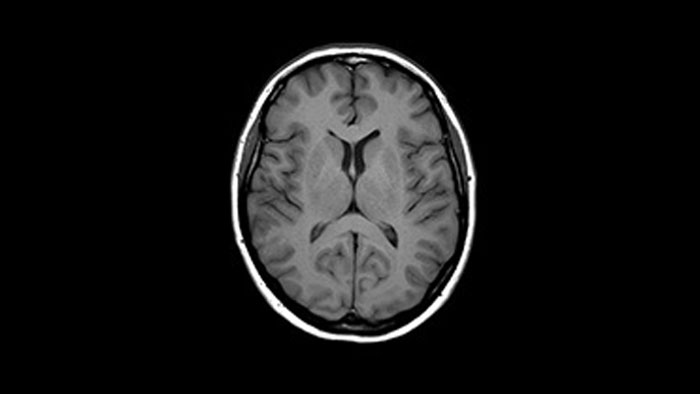

Bei einigen Untersuchungen, beispielsweise von Gehirn und Wirbelsäule, lässt eine hohe räumliche Auflösung sehr kleine Nerven und Gefäße besser erkennen. Um diese Auflösung zu erreichen, können mit Compressed SENSE 2D-MR-Scansequenzen durch schnellere 3D-Sequenzen ersetzt werden.

Mit Compressed SENSE lässt sich ein 2D-FLAIR-Scan mit einer Ausrichtung durch einen volumetrischen 3D-FLAIR-Scan mit mehreren Ausrichtungen ersetzen. Die Scandauer beträgt dabei lediglich dreieinhalb Minuten.

Ich erstelle häufig Bilder des Gehirns. Bisher haben wir die FLAIR-Sequenz mit einer Schichtdicke von 5 mm verwendet. Mit Compressed SENSE können wir jetzt einen volumetrischen 3D-Scan statt in sechs Minuten in etwa dreieinhalb Minuten durchführen.“

Dr. Mark Oswood, MD, PhD, Neuroradiologe, Hennepin Healthcare, Minneapolis, USA